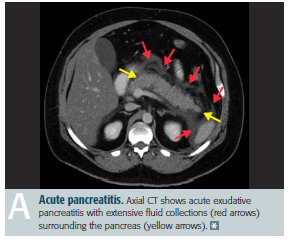

Acute pancreatitis